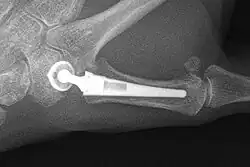

Joint replacement

The joint can be replaced with artificial material. An artificial joint is also referred to as a prosthesis. Prostheses are more problematic at the trapeziometacarpal joint compared to joints like the knee or the hips.

[27]Prostheses come in many varieties, such as spacers or resurfacing prostheses.

It’s not clear within the current literature that a prosthesis has any advantage over trapeziectomy.[27]

Overall, joint replacements are related to long-term complications such as subluxation, fractures, synovitis (due to the material used) and nerve damaging.In many cases revision surgery is needed to either remove or repair the prosthesis. Also note that usage of a joint replacement is heavy in costs.

The quality of the prostheses is improving and there is reason to believe this will have a positive effect on outcome in the years to follow.[27]